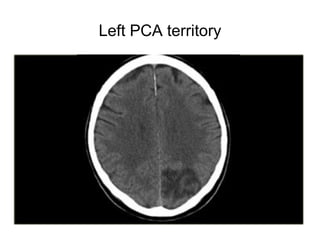

Left PCA territory